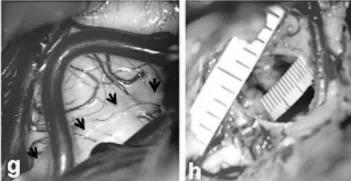

术中图片

巴教授通过外侧小脑上经小脑幕入路,艾丽以半坐位(c)接受手术。皮肤上标记左侧枕侧/枕下纵向切口(d)。剔除部分头发,为她保留了美丽的长发。

在手术暴露时,被盖外侧表面正常;箭头表示滑车神经的走行(g)。脑海绵状血管瘤完全切除后的术中照片显示2毫米尺度的空切除术腔(h)。术后轴向(e)和矢状(f)MRI证实病灶完全切除。